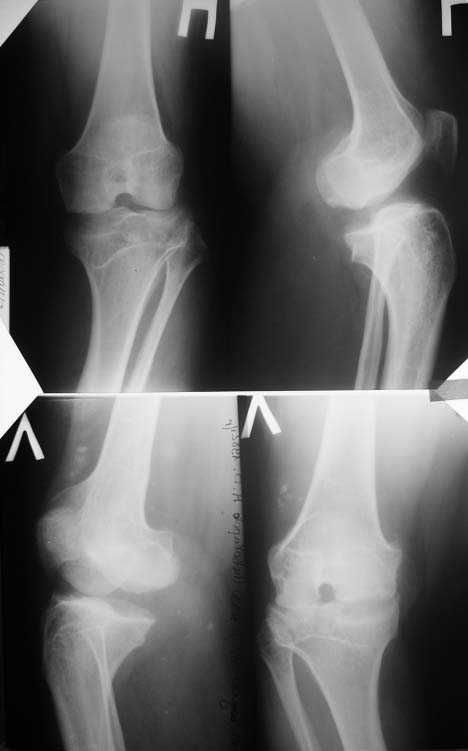

Прямая и боковая обоих коленных суставов

О коленях надо больше клинической информации, а главное чего хочет сам пациент.